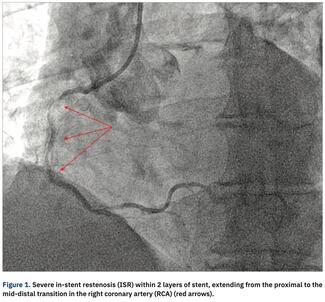

In-stent restenosis (ISR) is the Achilles’ heel of percutaneous coronary intervention (PCI). A common cause of ISR is an under-expanded stent secondary to under preparation of a target vessel with circumferential deep calcification. ISR...